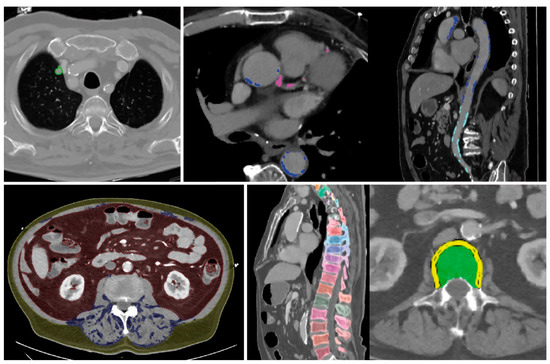

All findings resulting from the automated assessment are displayed in a structured “hAIco” (Heidelberg AI-based detection of Comorbidities) report (Figures S1 and S2). Along with the detailed quantitative information on findings, the report includes reference values if available and recommendations for additional diagnostic workup. According to the significance, findings are labelled by colors which is intended to support an intuitive report for physicians and patients. Findings with measured values beyond normal are marked in red. Green labelled results are within range. Values in between these two categories are marked yellow. Cross-sectional images are attached at the end of each report with demonstration of the organ segmentations and measurements, as well as highlighting the pathologic findings (Figure 2 and Figure 3) and the online supplementary material demonstrates the results of the comorbidity analysis of chest CT scans of two patients.

The algorithm-based, automated analysis of a contrast-enhanced thoraco-abdominal CT scan from a 75-year-old male patient, for the feasibility assessment of a Transcatheter Aortic Valve Implantation (TAVI) showed abnormal values of VFA, an indication for nutrition adjustment (Figure 2, Table 2, Figure S1: TAVI Patient). In addition to elevated TAG and AAC levels, a high artery calcium deposition was scored with the Agatson method at >300, recommending a high-intensity statin therapy [53,81,82,92]. Furthermore, an incidental pulmonary nodule was detected and classified as Lung-RADS grade 2, suggesting follow-up in 12 months with CT [87]. Bone mineral density acquisition showed pathologically reduced t-scores in need for additional diagnostic workup [19].

Figure 2. Example no. 1 ‘TAVI patient’—Summary of organ segmentations and pathological findings from left to right and top to bottom: pulmonary nodule of the right upper lobe, coronary and aortic calcifications, visceral, subcutaneous and intramuscular adipose tissue, and vertebral segmentations for assessment of BMD.